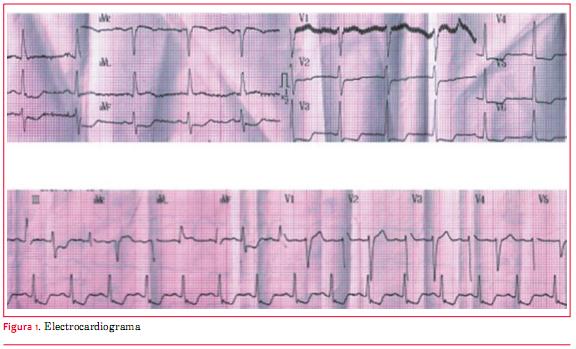

Paciente de 82 años de sexo masculino con antecedentes de tabaquismo e hipertensión arterial. Veinticuatro horas antes del ingreso presentó dolor retroesternal opresivo intenso durante un esfuerzo moderado, sin irradiaciones, acompañado de disnea, que calmó espontáneamente a los 15 minutos y por el cual no consultó. El día del ingreso reiteró nuevo episodio de dolor de iguales características pero de mayor intensidad, en reposo, acompañado de disnea y síndrome neurovegetativo, por el que consultó a las seis horas de iniciado el cuadro. Al ingreso se destacaba hipotensión arterial de 80/60 mmHg, estertores crepitantes en tercio inferior de ambos campos pulmonares y un soplo sistólico regurgitante en foco mitral de intensidad 2/6, irradiado a axila. Se realizó electrocardiograma en el que se comprobó infradesnivel del segmento ST de hasta 3 mm en DII, DIII y aVF y de V2 a V6 y supradesnivel del segmento ST de 1 mm en aVL (figura 1). Los marcadores cardíacos fueron positivos (CK total/MB 795/197 UI/l y troponina T 1,30 ng/ml). Se inició tratamiento antiisquémico con nitroglicerina i/v, persistiendo con ángor, siendo referido para cineangiocoronariografía de urgencia a las ocho horas de iniciado el segundo episodio de dolor. Esta se realizó por acceso radial derecho. Se comprobó que la arteria descendente anterior presentaba una lesión severa y extensa de tercio medio, el primer ramo diagonal una lesión severa proximal y oclusión proximal de uno de sus ramos de bifurcación, la arteria coronaria derecha una lesión moderada distal y el ramo descendente posterior una lesión crítica proximal (figuras 2 y 3). El procedimiento fue mal tolerado, con desaturación arterial de oxígeno por falla ventricular izquierda congestiva, extrasistolía ventricular frecuente e hipotensión arterial que requirió infusión de noradrenalina. Por este motivo y dado que el vaso culpable, probablemente el ramo de división ocluido del primer ramo diagonal, era un vaso de escaso desarrollo, se decidió no intentar una angioplastia coronaria. Se colocó balón de contrapulsación intraaórtico (BIAC). Por ecocardiograma (transtorácico y transesofágico) se comprobó rotura completa de músculo papilar anterior, insuficiencia mitral severa por eversión de la valva mayor de la mitral; función sistólica global conservada, sin alteraciones evidentes de la motilidad segmentaria (figura 4). El paciente evolucionó al shock cardiogénico refractario al tratamiento, falleciendo a las 12 horas de ingresado.